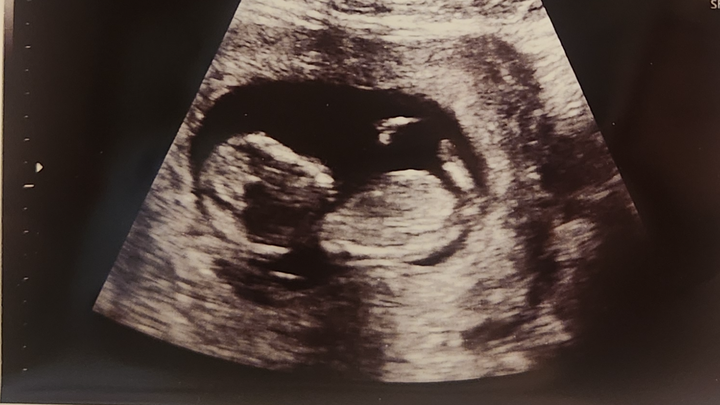

On Wednesday, I had a gut feeling something wasn’t right. I took the boys with me to the doctor, and I was right baby, Kaycen, no longer had a heartbeat. On Thursday, I was admitted to the hospital for surgery.